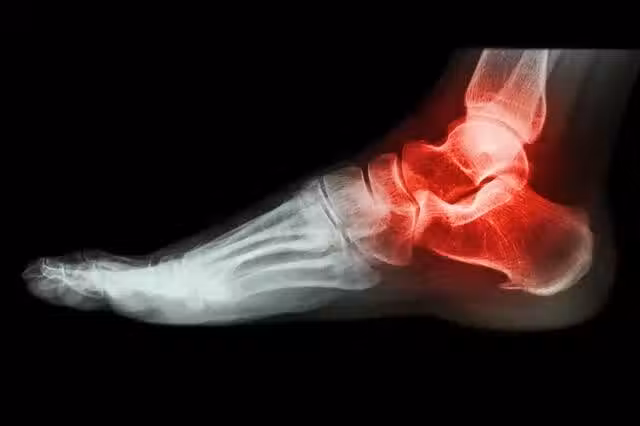

痛風是一種發作起來就會讓人感覺到異常疼痛的疾病,具體痛到什麼程度,恐怕只有痛風患者自己知道。

相信很多痛風患者都知道,痛風是因為患了高尿酸血症之後,沒有控制住病情,導致關節和周圍軟組織聚集大量的尿酸鹽晶體引起。

在發病的時候,患者的關節和軟組織會出現炎症,並且伴有痛風石沉積、關節損壞的情況。所以對於這個疾病的治療,控制尿酸值非常重要!